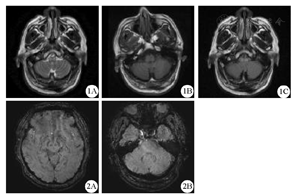

Cranial MR imaging of the patient Fig.2 Susceptibility weighted imaging of the patient

1A:T2WI呈高信号,1B:T1WI呈等信号,1C:FLAIR像呈高信号;2A:大脑皮层及中脑未见多发微出血,2B:脑桥、小脑未见多发微出血;FLAIR:液体衰减反转恢复序列

患者男性,53岁,因"阵发性头昏1年,加重伴走路不稳6月"于2017年3月1日入院。患者1年前无明显诱因出现头昏,表现为头昏沉感,不伴有天旋地转感及恶心呕吐,持续数小时至数天不等。近6个月来症状逐渐加重,伴走路不稳,姿势异常,步距增宽,不能走直线,偶有视物双影。于2017年2月8日就诊于当地医院,按"脑梗死"给予治疗,症状未见明显好转,遂来我院。既往史:糖尿病史2月,规律监测血糖示血糖控制可;高血压病史3年;长期大量吸烟史;否认牛羊接触史,否认肝炎、结核等传染病史,否认家族遗传病史。体检:血压157/90 mmHg(1 mmHg=0.133 kPa),心率72次/min。神清语明,高级智能正常,双眼向各方向活动充分,双眼向右侧注视时有水平细小眼震,辐辏反射正常;双上肢腱反射略活跃,双下肢腱反射正常引出;双侧深浅感觉对称存在,闭目难立征(+),双侧指鼻试验、跟膝胫试验基本稳准,左侧Babinski征可疑阳性,颈软,脑膜刺激征(-),余查体未见异常。辅助检查:头颅MRI(2017年2月10日于当地医院)示右侧基底节区软化灶,延髓异常信号,增强后未见异常强化病灶。复查头颅MRI(2017年3月3日于我院)示双侧延髓腹侧异常信号(图1)。颈动脉超声、经颅多普勒超声、脑干诱发电位及视觉诱发电位均无异常。头颅磁敏感加权成像(SWI)未见脑内多发微出血(图2)。腰椎穿刺检查:脑脊液无色透明,压力110 mmH2O(1 mmH2O=9.8 Pa)。脑脊液常规检查:蛋白0.37 g/L,潘氏反应阴性,白细胞计数1×106/L,IgG 18.1 g/L。细胞学检查:白细胞计数2×106/L,偶见淋巴细胞,未见异常细胞。脑脊液IgG指数、寡克隆区带、髓鞘碱性蛋白、抗水通道蛋白抗体等相关检查未见明显异常。糖化血红蛋白7.3,生化、肝功、血氨、外科综合、风湿三项、免疫五项、男性肿瘤标志物、甲功五项等检查未见明显异常。入院后按"脱髓鞘疾病"给予甲强龙80 mg,1次/d静脉点滴,1周后症状无缓解,故停用激素。复查头颅MRI示病灶未见明显改变。